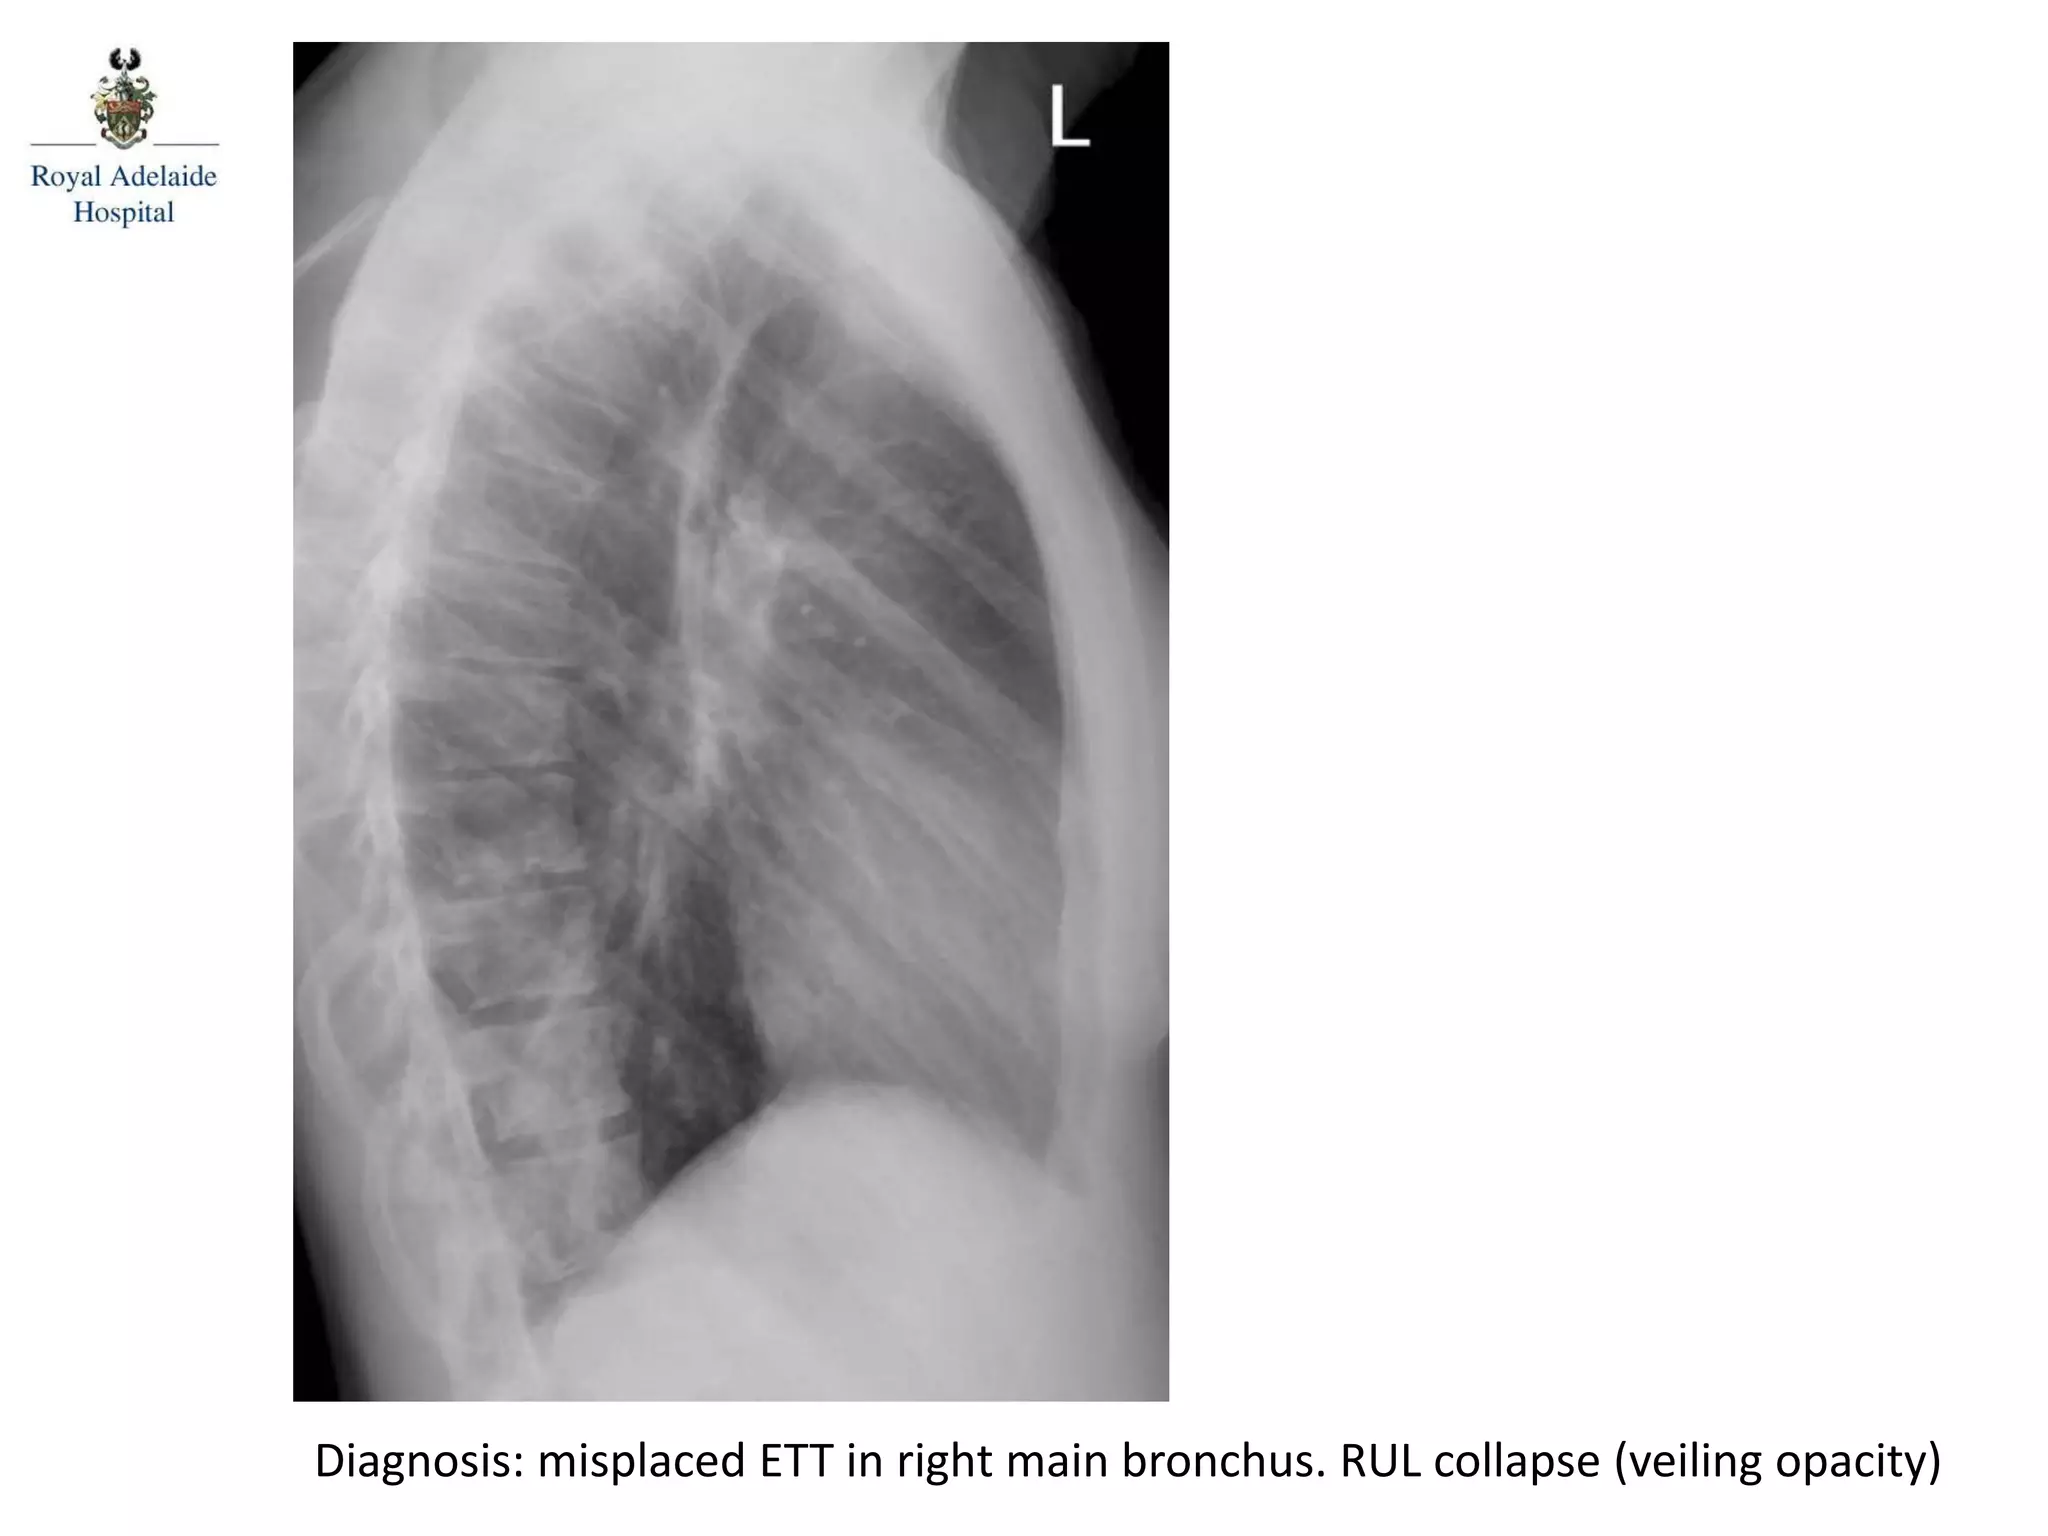

Diagnosis: misplaced ETT in right main bronchus. RUL collapse (veiling opacity)